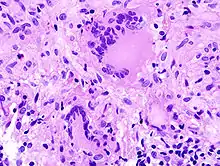

Fremdkörper-Riesenzellen bei Aspirationspneumonie, Autopsiepräparat, H&E.

Riesenzelle und diffuser Alveolarschaden bei SARS-Infektion.

Riesenzelle mit intrazytoplasmischen inclusion bodies bei Masernpneumonie, Histopathologie.